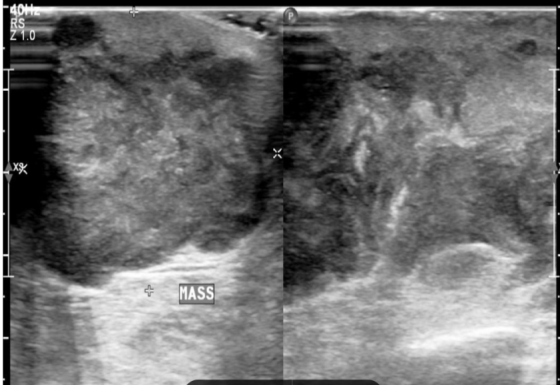

A 53 y old man was presented to our hospital with a progressively enlarging lump in his left breast with surface ulceration. He had multiple neurofibromas all over his body. Physical examination revealed a hard mass in the left breast with skin involvement and erythema of the skin. He underwent an ultrasound that revealed a large lobulated heterogeneous (fig. 1) wider-than-taller mass lesion at the 2 o'clock position in the periareolar region with posterior acoustic enhancement with pectoralis muscle infiltration and overlying skin thickening and ulceration (BIRAD V). Also, left axillary lymphadenopathy (fig. 2) was noted.

Fig. 1: Ultrasound picture showing hypoechoic lobulated mass infiltrating chest wall